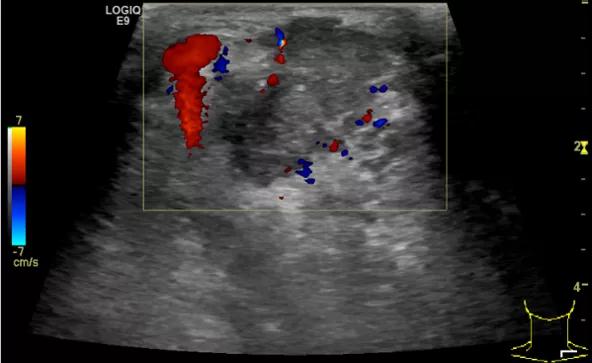

随后,徐栋教授进一步分享了五个临床实战病例,带来了更直观的热消融治疗经验。第一个病例是62岁肺癌患者,术后1年余发现双侧锁骨上淋巴结复发,侵犯神经,存在静脉回流、淋巴回流障碍,肿胀、疼痛非常明显。影像显示患者淋巴结边界不清、形态不规则,存在浸润,血流强化增强。由于患者在系统治疗后进展,且主要目的缓解症状、减瘤。局麻下行热消融术,从后向前逐层消融,热消融之后超声造影即刻评估显示完全充盈缺损,完全覆盖病灶。

(病例1图例)

第二例是食管癌患者,术后半年余锁骨上固定淋巴结可触及肿大,疼痛非常明显,系统治疗后无缓解,患者希望通过局部处理缓解症状。造影显示强化信号明显,结节部分区域坏死,故主要针对强化区域从后向前的逐层的消融,皮下进行液体隔离减少烫伤。热消融后影像显示血流增强消失,弹性、硬度增高,一个月后复查显示充盈缺损,完全消融,疗效远超预期。

(病例2图例)